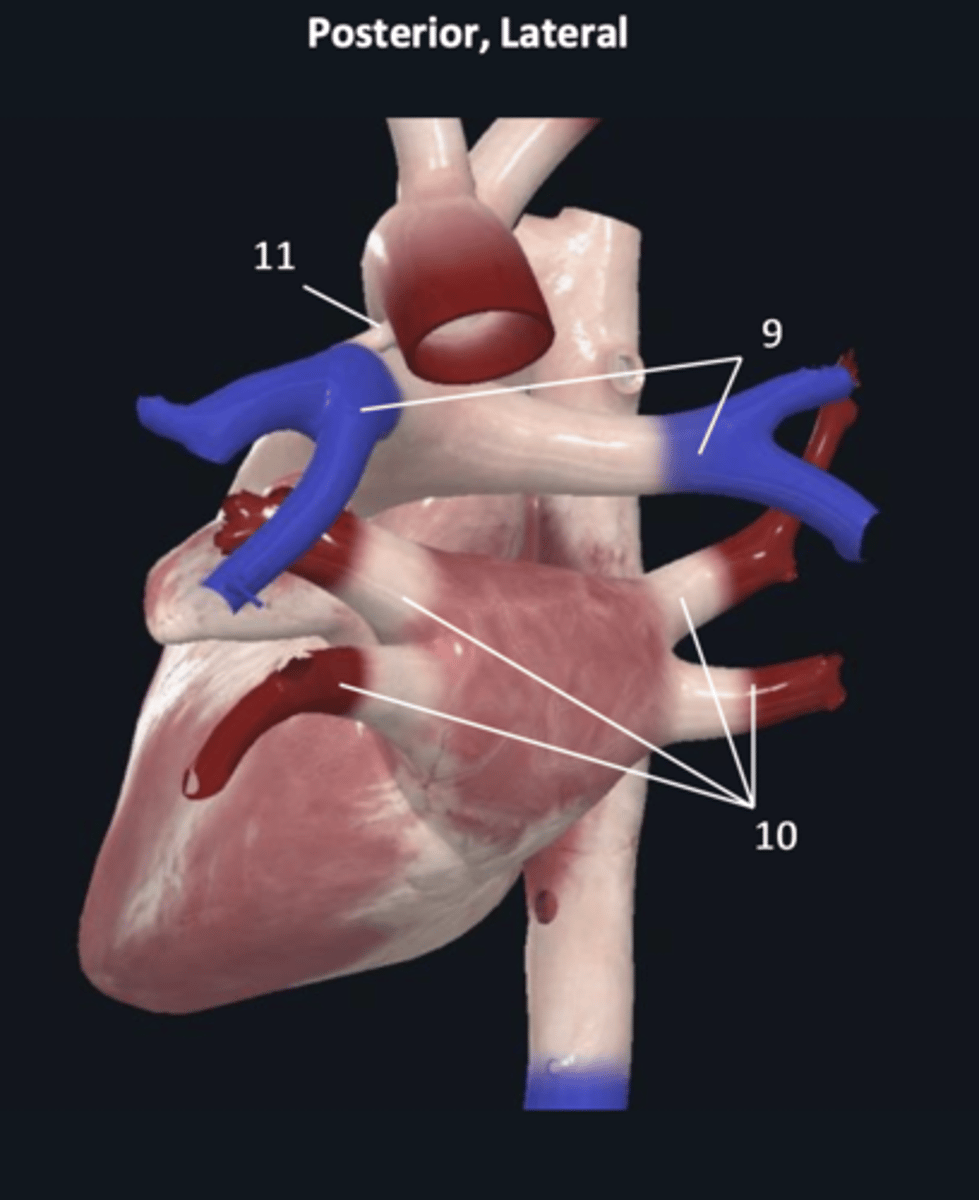

pulmonary trunk

8

pulmonary arteries

9

pulmonary veins

10

ligamentum arteriosum

11

right coronary artery

1 (red)

great cardiac vein

3

posterior left ventricular artery

6

posterior vein of left ventricle

7

coronary sinus

8

right posterolateral artery

9

middle cardiac vein

10

posterior interventricular artery

11

right marginal artery

12

small cardiac vein

13